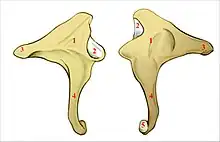

L'enclume a une forme de molaire constitué d'un corps cubique et de deux branches. L'une supérieure et horizontale forme la branche courte, et l'autre inférieure et verticale forme la branche longue

Branche courte de l'enclume

La branche courte de l'enclume (ou branche courte de l'incus ou courte apophyse de l’enclume ou branche horizontale de l’enclume) est un prolongement osseux en forme de cône aplati de dehors en dedans. Elle s'étend horizontalement en arrière du corps de l'enclume. Son sommet, qui correspond à l'extrémité postérieure s'appuie sur l'échancrure située à l'angle inférieur de l'orifice antérieur de l'aditus ad antrum,